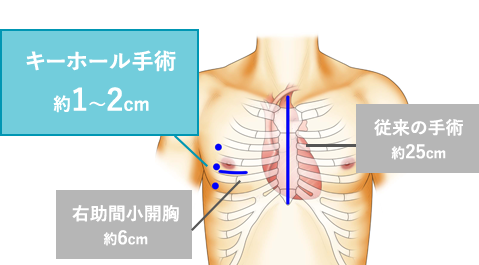

“ダビンチ”キーホール手術は、手術支援ロボット“ダビンチ(da Vinci Surgical System)”を用いたロボット手術です。開胸することなく、骨を切らず、数カ所のキーホールからすべての操作が遂行できるので、術中の出血が少なく、術後の痛みも軽く、また大きな傷が残らないため美容的にも優れています。従来のように人工心肺などを使用して遂行していた手術が“ダビンチ(da Vinci Surgical System)”の出現により劇的に変化し、術後経過や術中の体への負担が軽減できるようになりました。“ダビンチ(da Vinci Surgical System)”のような内視鏡手術の進歩は心臓だけでなく、すべての領域で目覚ましい発展を遂げています。現在では珍しいものでは無く標準の手術方法として認められる傾向にあり、新たなアプローチとして広い分野で採用されています。

手術支援ロボット“ダビンチ”を使用したロボット手術は、骨を切らずに小さな傷口のみでオペを行い、出血量・痛みの減少を実現します。早期の社会復帰が可能な手術です。

従来の治療アプローチと

ダビンチ“キーホール手術”の違い

骨を切ることなく数カ所の

キーホールからすべての操作を